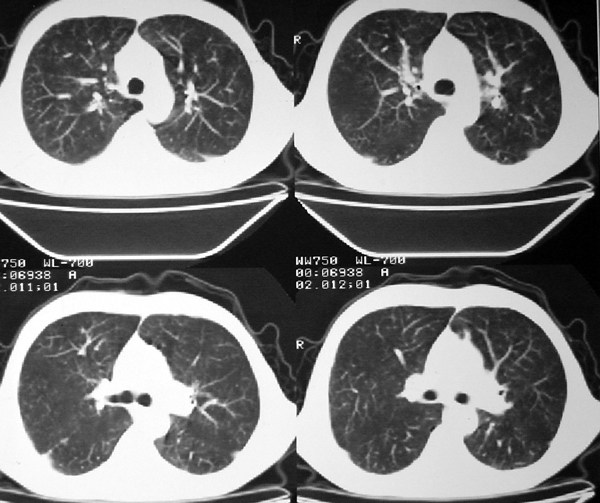

右肺囊实性占位 患者拒绝穿刺活检  近期始终间断性发高烧 使用消炎控制, 左鼻翼部有多发皮肤溃疡

双肺呈毛玻璃状,胸膜旁有多个小囊状气腔。右下囊实性病灶内有园形气体影,边缘光滑,与之相连的胸膜稍增厚,间断发热,抗炎效果不好。考虑机会性感染可能性大。

右下肺占位性病变,其边缘较光整无明显分叶,似有包膜,邻近胸膜无凹陷征及牵拉征象,包块内见数个大小不等气液面及不规则透亮影,纵隔未见明显淋巴结肿大。结合上次ct检查,考虑:炎性包块或真菌感染包块可能性大,周围型肺癌可能性小。